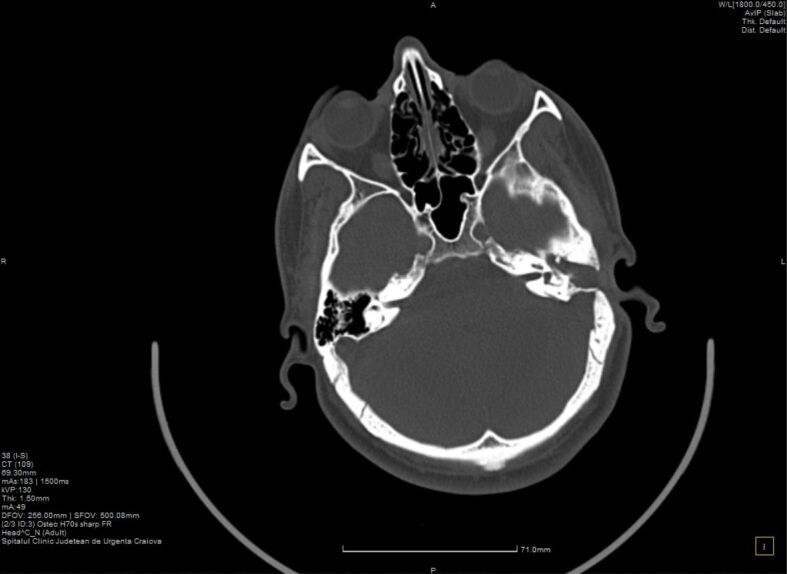

胆脂瘤是一种耳科病变,可发生于任何年龄,并可导致各种并发症,包括面瘫、颅内脓肿、听力损失、静脉血栓形成等。胆脂瘤即使被认为是一种良性疾病,但由于其侵袭性,复发的风险也很高。我们描述了一例复发性胆脂瘤病例,患者为一名年轻男孩,在 16 岁至 19 岁(2019 年至 2022 年)期间,曾因慢性耳流脓和听力下降接受过三次手术治疗。小儿胆脂瘤更容易复发。考虑到手术切除是目前唯一的治疗方法,了解胆脂瘤病变扩展的生物学特性对于进一步改善治疗管理非常重要。对与手术方法相关的血管生成、慢性炎症和免疫浸润进行深入研究可能是预防胆脂瘤复发的未来方向。

Cholesteatoma is an otologic pathology that can occur at any age and can lead to a variety of complications including facial palsy, intracranial abscess, hearing loss, venous thrombosis. Cholesteatoma, even if considered a benign condition, associates high risks of recurrency due to its invasiveness. We describe a case of recurrent cholesteatoma in a young boy who presented chronic ear discharge and hearing loss for which had undergone three surgical interventions between the ages of 16 and 19 years old, from 2019 to 2022. Pediatric cholesteatoma is more prone to recurrency. Considering surgical excision as the only treatment at the current moment, it is highly important to understand the biology of cholesteatoma lesional extension for further treatment management improvement. Good research of angiogenesis, chronic inflammation and immune infiltration correlated with surgical approach may be the future for preventing cholesteatoma recurrency.